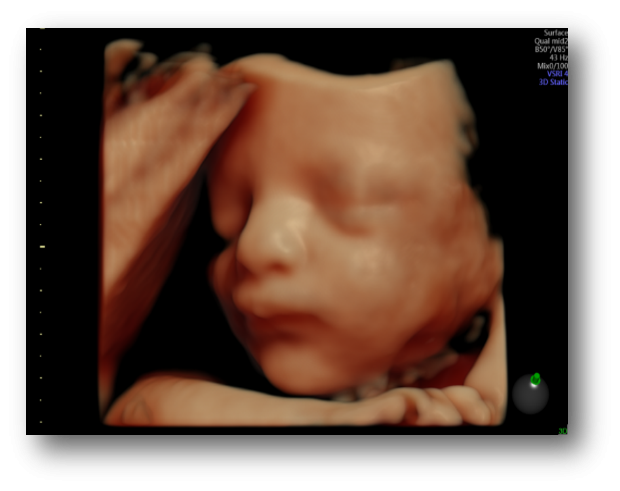

HDlive, HDlive Silhouette e HDlive Studio per una rappresentazione anatomica realistica

SonoRender per volumi 3D definiti e uniformi

Rendering 3D/4D ad alta fedeltà

Diagnostica fetale avanzata